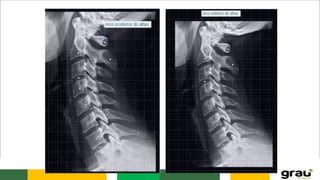

CURVATURAS: Primárias e secundarias

IMPORTÂNCIA CLINICA: hipercifose, hiperlordose escoliose

C. LOMBAR

5 vértebras (L1 a L5)

Corpo robusto

Processo espinhoso laminar

COLUNA VERTEBRAL CURVATURAS: Primáriase secundarias IMPORTÂNCIA CLINICA: hipercifose, hiperlordose escoliose Caracteristicas das vértebras permitem identificar a que região pertencem.